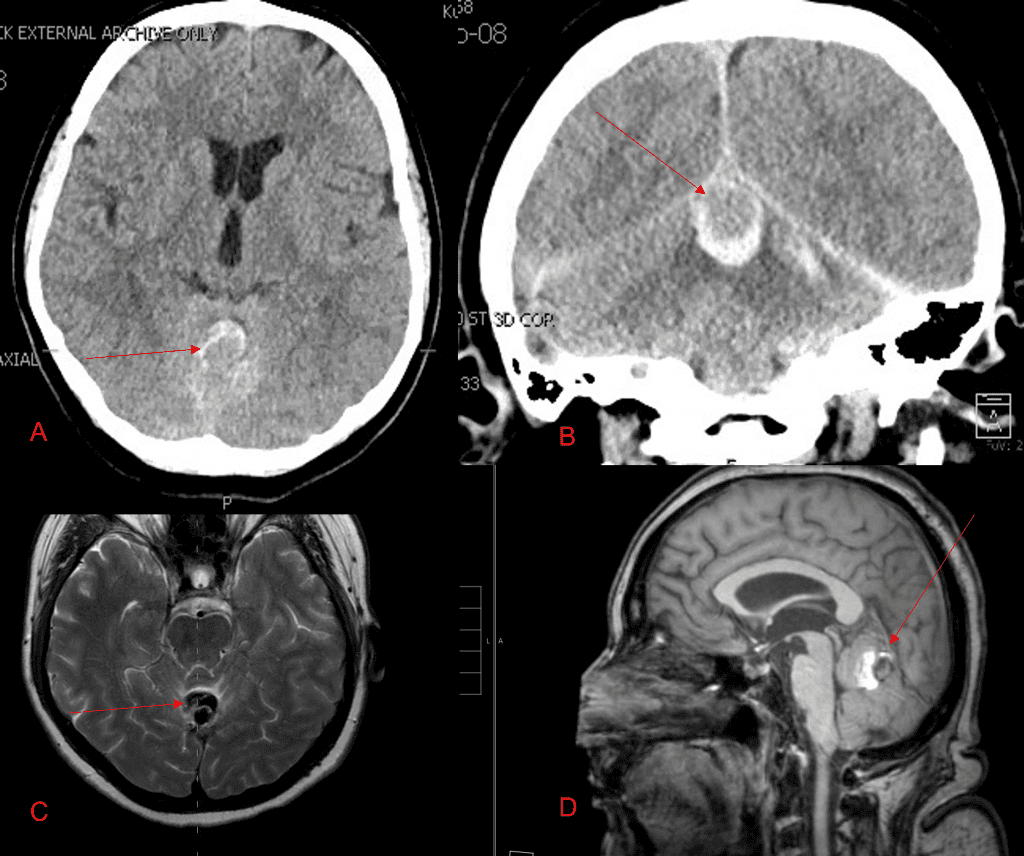

Endovascular:

Hydrocephalus and Brainstem Tumor

Author: Jonathan L. Brisman M.D., F.A.C.S., Read More!